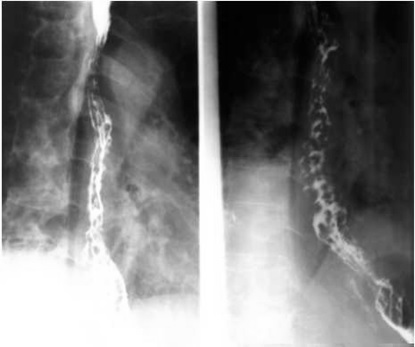

05卷-5.男性,胸骨后隱痛一年,請選擇正確答案(本題滿分2.00分)

A.食管癌

B.食道靜脈曲張

C.食道賁門失遲緩綜合征

D.食管憩室

本題答案:B

【該題針對“ 造影-食管靜脈曲張 ”知識點進行考核】